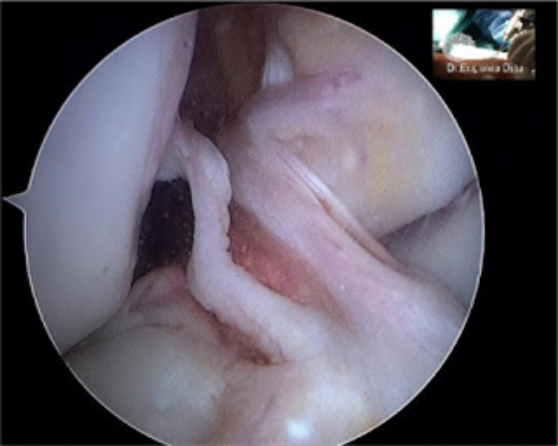

El ligamento se reconstruye mediante Artroscopia de rodilla, procedimiento mínimamente invasivo y con un postoperatorio mucho más favorable.